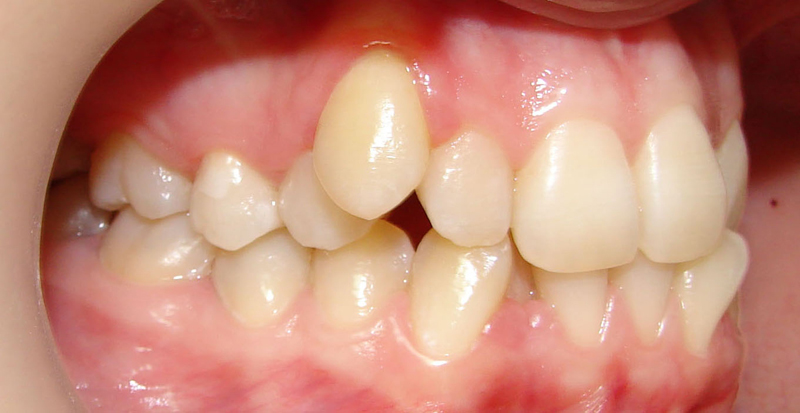

Начну с самого простого. Мальчик, 6 лет. Носил съемную плстинку 4 мес. В таком возрасте брекеты еще, как правило, не используют.

А это уже молодой человек 10 лет. Тоже получилось справиться без удаления. Хоть оно и было показано. Но мальчик очень упорно носил специальные аппаратики и резиночки. Покажу со всех сторон. Этот случай победил в конкурсе на конференции